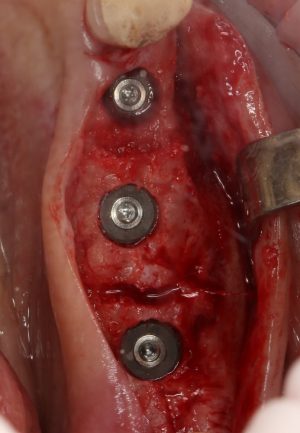

Помимо этого, один из этапов лечения периимплантита предполагает «превращение» субгингивального имплантата в трансгингивальный (подробности здесь>>). Описанную в статье методику можно считать успешной —  она, пусть и не восстанавливает уровень костной ткани вокруг имплантатов, но помогает избежать развития заболевания и потери имплантатов вообще: